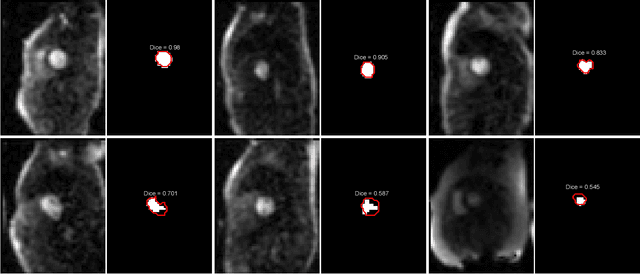

Abstract:Quantification of myocardial perfusion has the potential to improve detection of regional and global flow reduction. Significant effort has been made to automate the workflow, where one essential step is the arterial input function (AIF) extraction. Since failure here invalidates quantification, high accuracy is required. For this purpose, this study presents a robust AIF detection method using the convolutional neural net (CNN) model. CNN models were trained by assembling 25,027 scans (N=12,984 patients) from three hospitals, seven scanners. A test set of 5,721 scans (N=2,805 patients) evaluated model performance. The 2D+T AIF time series was inputted into CNN. Two variations were investigated: a) Two Classes (2CS) for background and foreground (LV mask); b) Three Classes (3CS) for background, foreground LV and RV. Final model was deployed on MR scanners via the Gadgetron InlineAI. Model loading time on MR scanner was ~340ms and applying it took ~180ms. The 3CS model successfully detect LV for 99.98% of all test cases (1 failed out of 5,721 cases). The mean Dice ratio for 3CS was 0.87+/-0.08 with 92.0% of all test cases having Dice ratio >0.75, while the 2CS model gave lower Dice of 0.82+/-0.22 (P<1e-5). Extracted AIF signals using CNN were further compared to manual ground-truth for foot-time, peak-time, first-pass duration, peak value and area-under-curve. No significant differences were found for all features (P>0.2). This study proposed, validated, and deployed a robust CNN solution to detect the LV for the extraction of the AIF signal used in fully automated perfusion flow mapping. A very large data cohort was assembled and resulting models were deployed to MR scanners for fully inline AI in clinical hospitals.